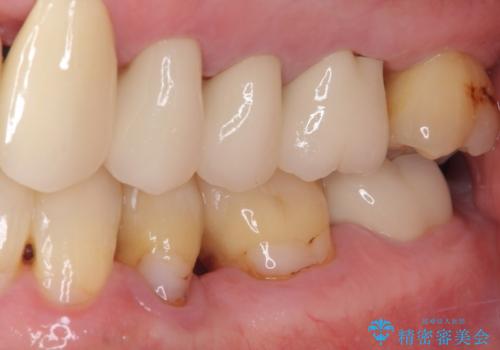

上の歯は見た目を良くしたいというご希望があったため、歯周外科処置を行った歯についてはセラミッククラウンで補綴することとしました。

気になっていた歯の痛みや歯肉からの出血がなくなり、改善したいと思っていた外見も綺麗に仕上がり、大変満足していただきました。